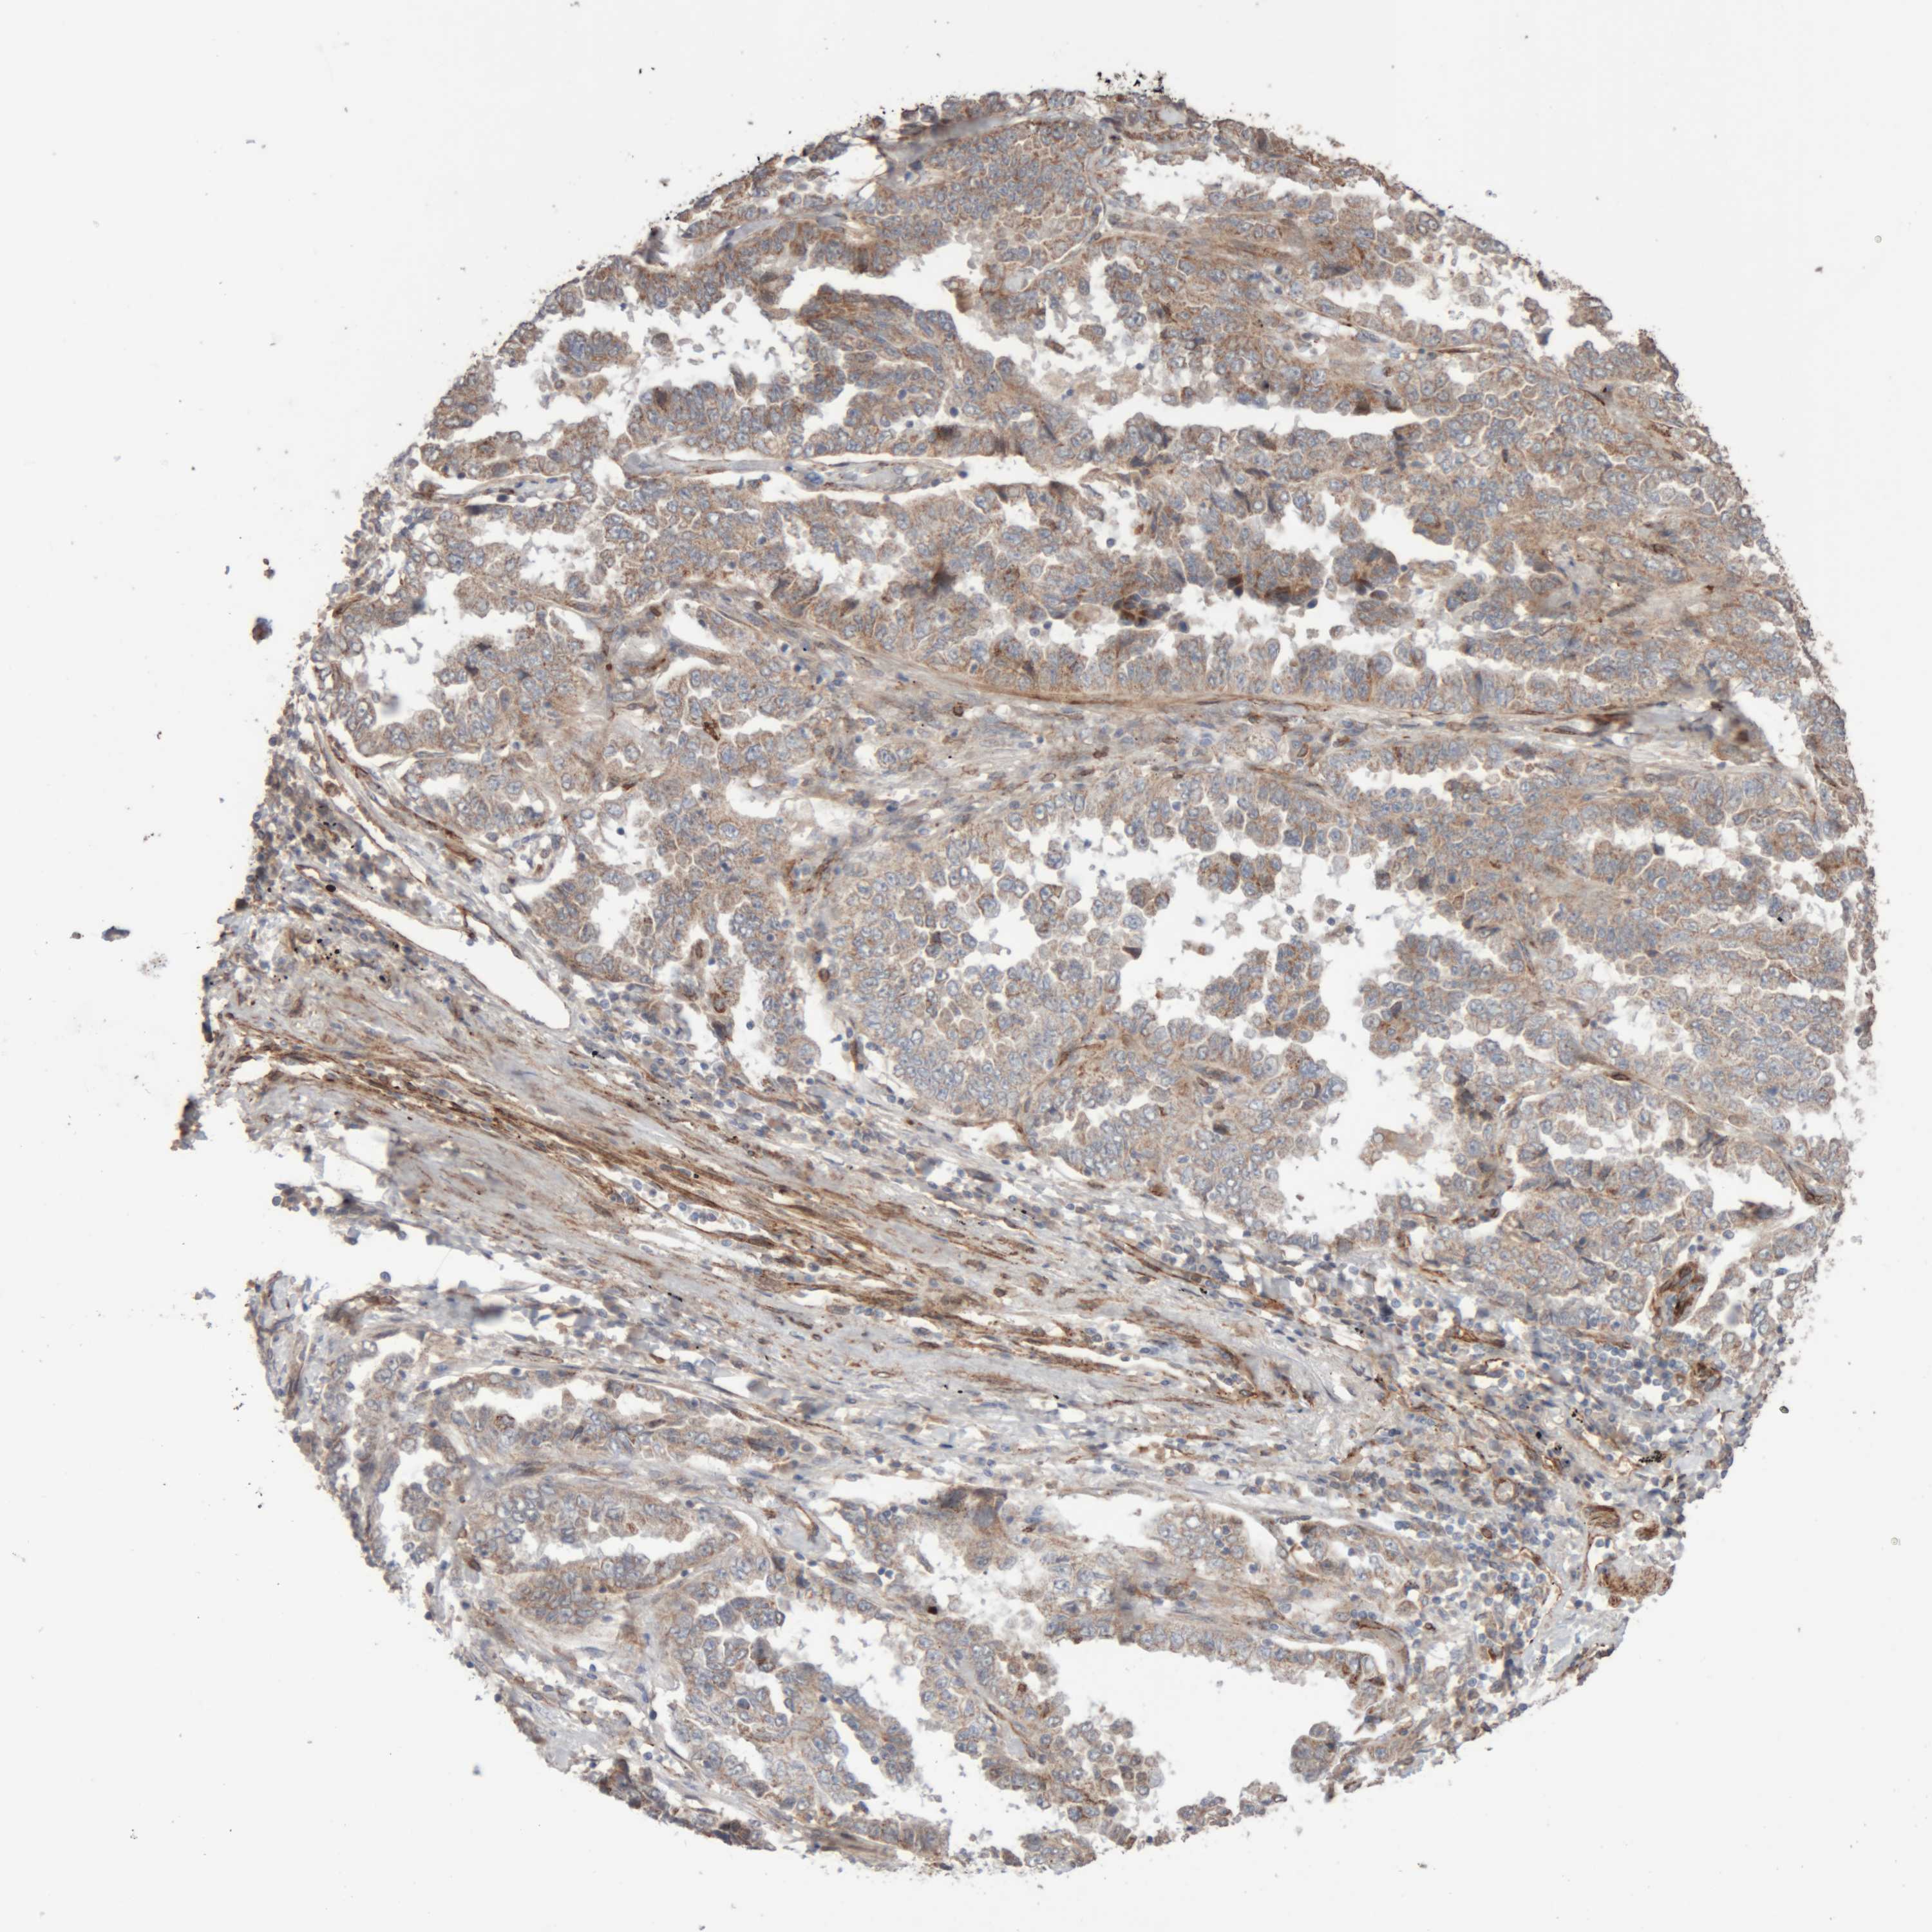

CANCER LUNG CANCER Show tissue menu

LUAD TCGA LUAD VALIDATION LUSC TCGA LUSC VALIDATION PROTEIN LUAD CPTAC PROTEIN LUSC CPTAC PROTEIN EXPRESSION